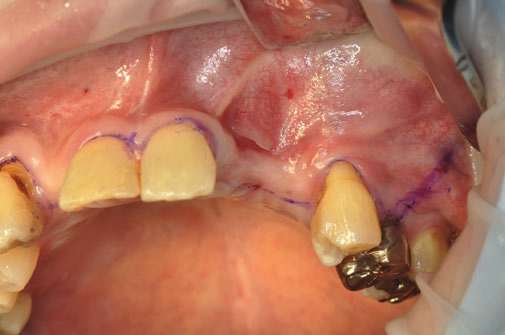

GBR法では、骨の不足している部分に人工骨の粉末を入れ、骨の再生を誘導します。

GBR法で骨を造り、その後にインプラント手術を行います。

GBR法の手術の流れを写真でご紹介しています。

どのような手術を行うのか、事前に知っていただけたらと思います。